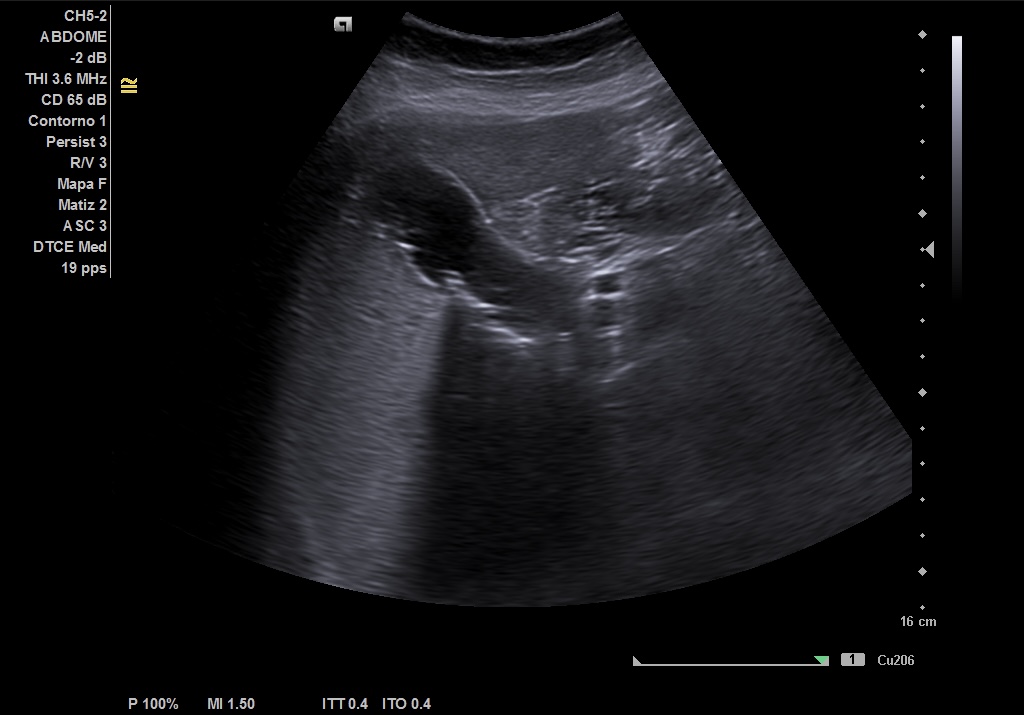

Hallazgos ecográficos

Realizamos ecografía abdominal en el Centro de Salud en el momento de la consulta y visualizamos: Colelitiasis y dilatación de la vía intra y extrashepática sin observar claramente causa obstructiva.

• Nueva ECO de abdomen y colangioRMN en las que se observa: colelitiasis. Vía intra y extrahepática dilatada, sugestivo de coledocolitiasis distal de 5 mm, que se extrae con CPRE.

Pudimos confirmar que se trataba de una ictericia por obstrucción de vía biliar secundaria a litiasis de vesícula, con mismas imágenes encontradas en ECO reglada y en RMN realizadas en centro Hospitalario que las halladas en el Centro de Salud.